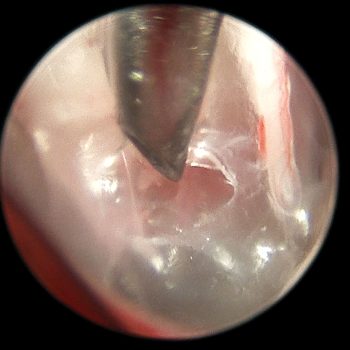

Diagnostyka endoskopowa zewnętrznych przewodów słuchowych (Otoendoskopia)

Głębokie płukanie przewodów słuchowych w znieczuleniu ogólnym

Myringotomia (nakłucie błony bębenkowej z oczyszczeniem z wydzieliny zapalnej) w celu diagnostyki i leczenia zapalenia ucha środkowego i wewnętrznego

Usuwanie ciał obcych (kłosy, bezoary)

Pobieranie biopsji tkanek zmienionych

Resekcję zmian nowotworowych w obrębie ucha zewnętrznego, także przy użyciu lasera